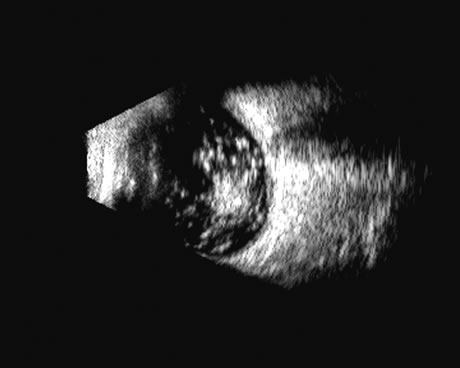

Fig. 16. 3D depiction of a retinal detachment can be helpful in situations in which there is ambiguity among retina, choroid, and schisis. The 3D rotatable display can be perceived from different perspectives, often aiding in the certainty of diagnosis.